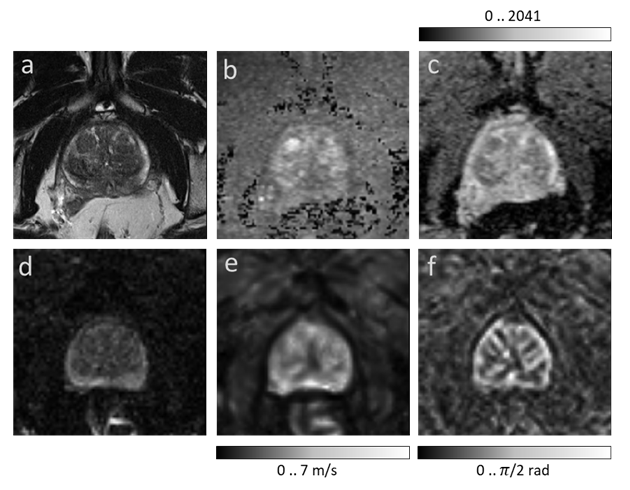

Refer to caption

Figure 2: Image augmentation using elastic deformation. First column shows the reference non-augmented T2w images in the first row and MRE magnitude maps (mag) in the second row. Augmented images are shown in the remaining columns: first row: T2w, ADC, and DWI_b. Second row: mag, SWS and φ𝜑\varphi.

2.3 Image preparation and augmentation

Since T2w, DWI, and MRE images had different resolutions, all images were resampled to a common resolution of 0.5 mm isotropic edge length. Images of the same size and resolution were obtained by positioning a cropping window with a size of 256x256 pixels at the center of each 3D imaging volume. For image augmentation, 9 random elastic deformations were applied to the original images to increase the number of training sets. As described in Simard et al. , elastic deformation can be driven by two main parameters: σ𝜎\sigma, which represents the elasticity coefficient, and α𝛼\alpha, which represents a scaling factor that controls the amplitude of the deformation. The two parameters were set to α𝛼\alpha = 21 and σ𝜎\sigma = 512. Examples of augmented images are provided in Figure 2.